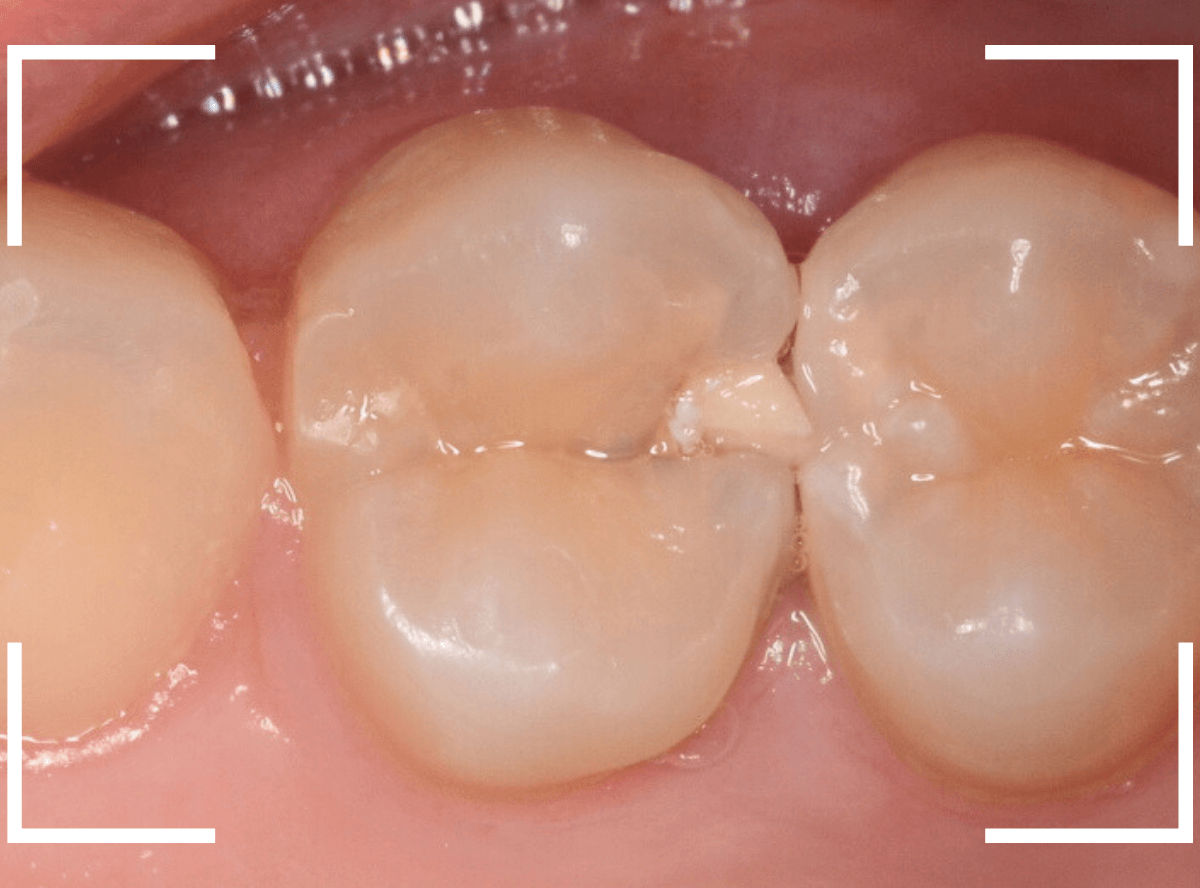

Case.1 奥歯のスキマが大きな虫歯!

他の歯の治療目的で来院された患者さんです。

全体検査の際、ちょっとこの歯、アヤシイなと思いましたが、確証はありませんでした。

(この写真で改めて見ると、かなりアヤシイと思いました)

レントゲン写真で確認すると、かなり大きな虫歯でした。

後日、改めて時間をお取りして、麻酔をかけて治療を開始です。

歯の表面を少し削ると、ボロッと虫歯が出てきました(>_<)

歯と歯の間の虫歯は、大抵は両方の歯に広がっている事がほとんどです。

今回のケースも、隣の歯まで、虫歯は広がっています。

最終的には、かなり神経に近いところまで虫歯が進んでいました。

もう少し遅かったら、危なかったと思います。

他の歯の治療で来院された事が、幸運でした。

しばらく経過観察した後、特に症状がありませんでしたので、隣の歯をレジンで治療後、ジルコニア・インレー(70,000円(税込み/2024年1月現在))で治療することにありました。

治療後の写真です。

特に症状もなく、審美性も高く治療することができました♪